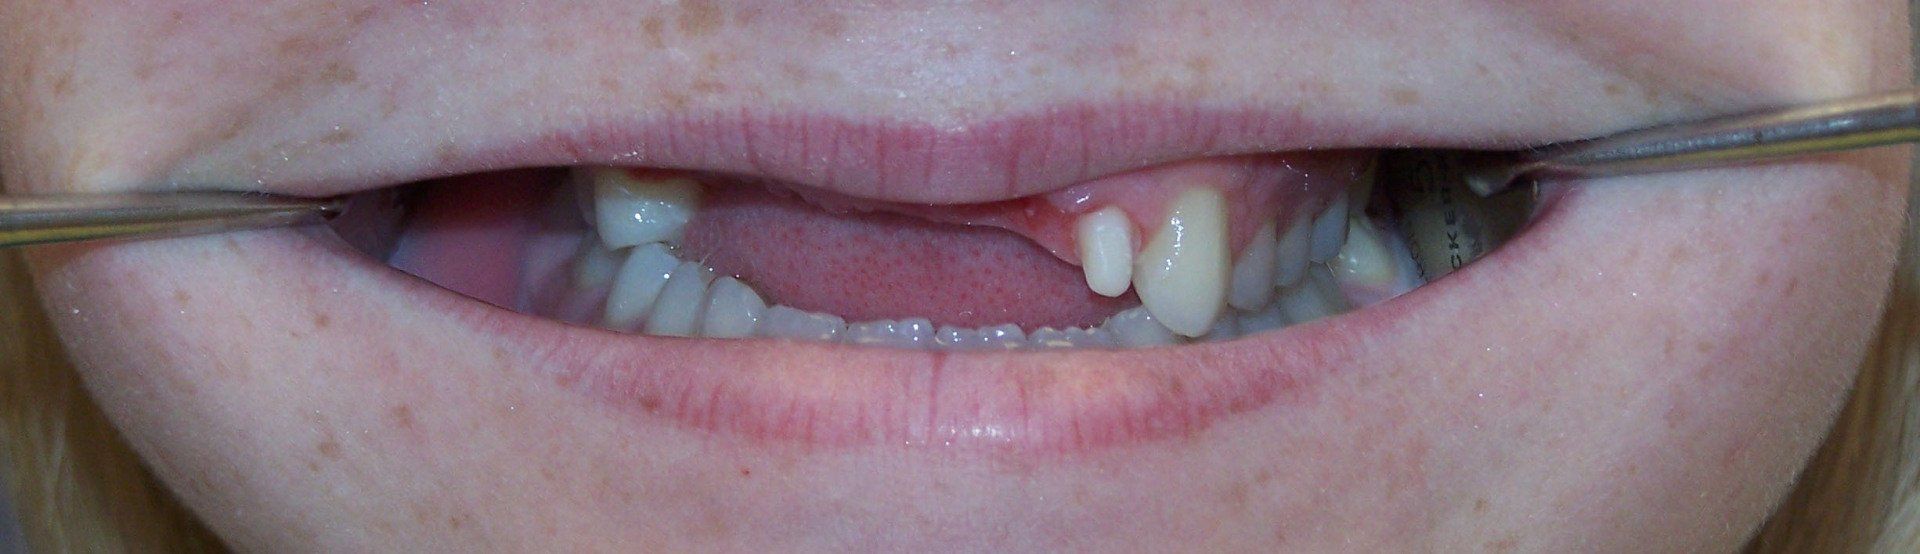

Nancy Before

Button

Nancy After